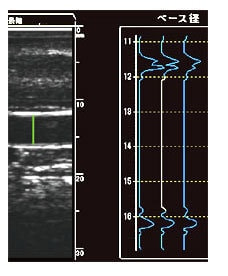

特徴3:Aモード計測により高い再現性の実現

血管径計測は、Bモード画像の5倍の分解能を持つAモード波形による計測を採用することにより 検者間誤差を少なくし、高い再現性を実現しています。

特徴4:トレンドグラフで真の最大拡張径を捉える

駆血開放後、血管が最も拡張する時間は30~90秒程度と個人差があります。 この個人差を、一拍ごとの血管径変化をトレンドグラフで表示する事により、最も血管が拡張した拍を捉えることができます。 これにより、真の最大拡張径によるFMD値の算出を可能としています。